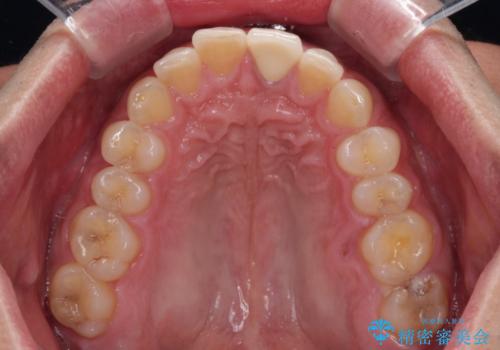

- 神経を取り除いたことで変色した前歯を気にして来院された患者様です。

根管治療はやり直さずに、ファイバーポストを使用した土台を植立してオールセラミッククラウンにて補綴することとしました。

神経を取り除いた歯は時間とともに変色してきます。

クリーニングやホワイトニングでは改善できないため、オールセラミッククラウンなどによる補綴治療が必要となります。